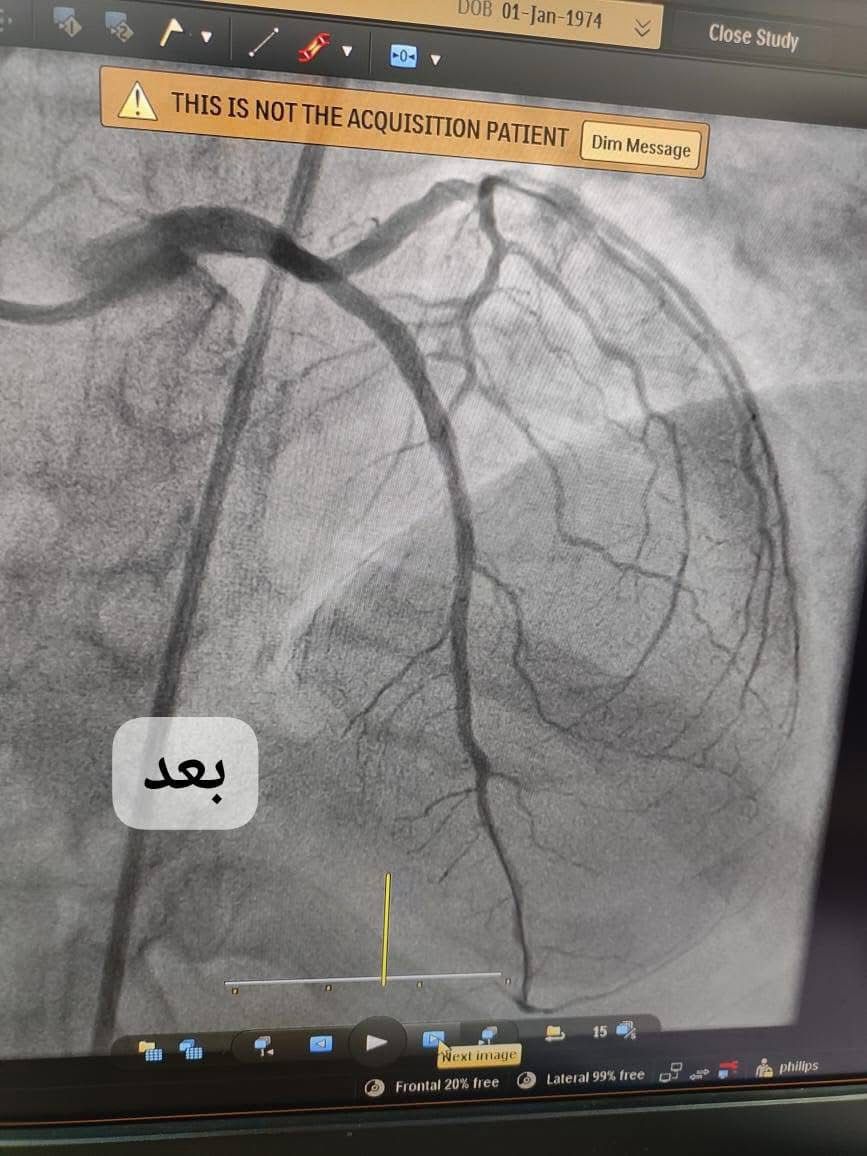

شفق نيوز/ شهد مستشفى الناصرية للقلب، ليلة حافلة بالإنجازات الطبية، حيث نجح فريق القسطرة القلبية في إجراء 4 عمليات طارئة لإنقاذ مرضى من مختلف أقضية ونواحي ذي قار، بعدما تعرضوا لأزمات قلبية حادة تطلبت تدخلاً عاجلاً.

وقال أخصائي أمراض القلب ورئيس الفريق الطبي الدكتور فريد مراد العسكري في تصريح ورد لوكالة شفق نيوز، إنه "من بين الحالات كانت هناك مريضة تبلغ من العمر 70 عامًا من قضاء سوق الشيوخ، وصلت بحالة حرجة جراء انسداد تام في الشريان الأيسر الرئيسي، مع تأريخ مرضي يشمل ارتفاع ضغط الدم المزمن والتدخين".

واضاف العسكري، ان "المريضة خضعت لعملية قسطرة عاجلة، حيث تم فتح الشريان وتركيب شبكة علاجية، مما أنقذ حياتها في لحظات حاسمة".